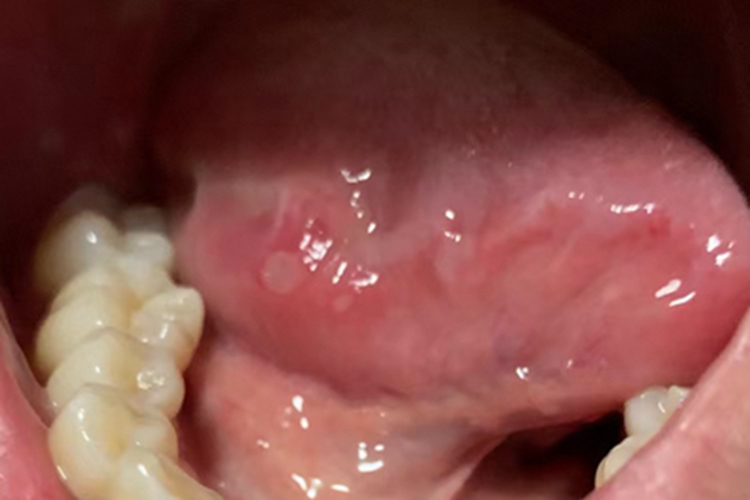

口腔溃疡可发生在舌下,可表现为舌下有圆形或椭圆形的白色斑块,斑块边界清晰,周边发红,患者自觉有疼痛不适感,在舌头活动时疼痛加重。